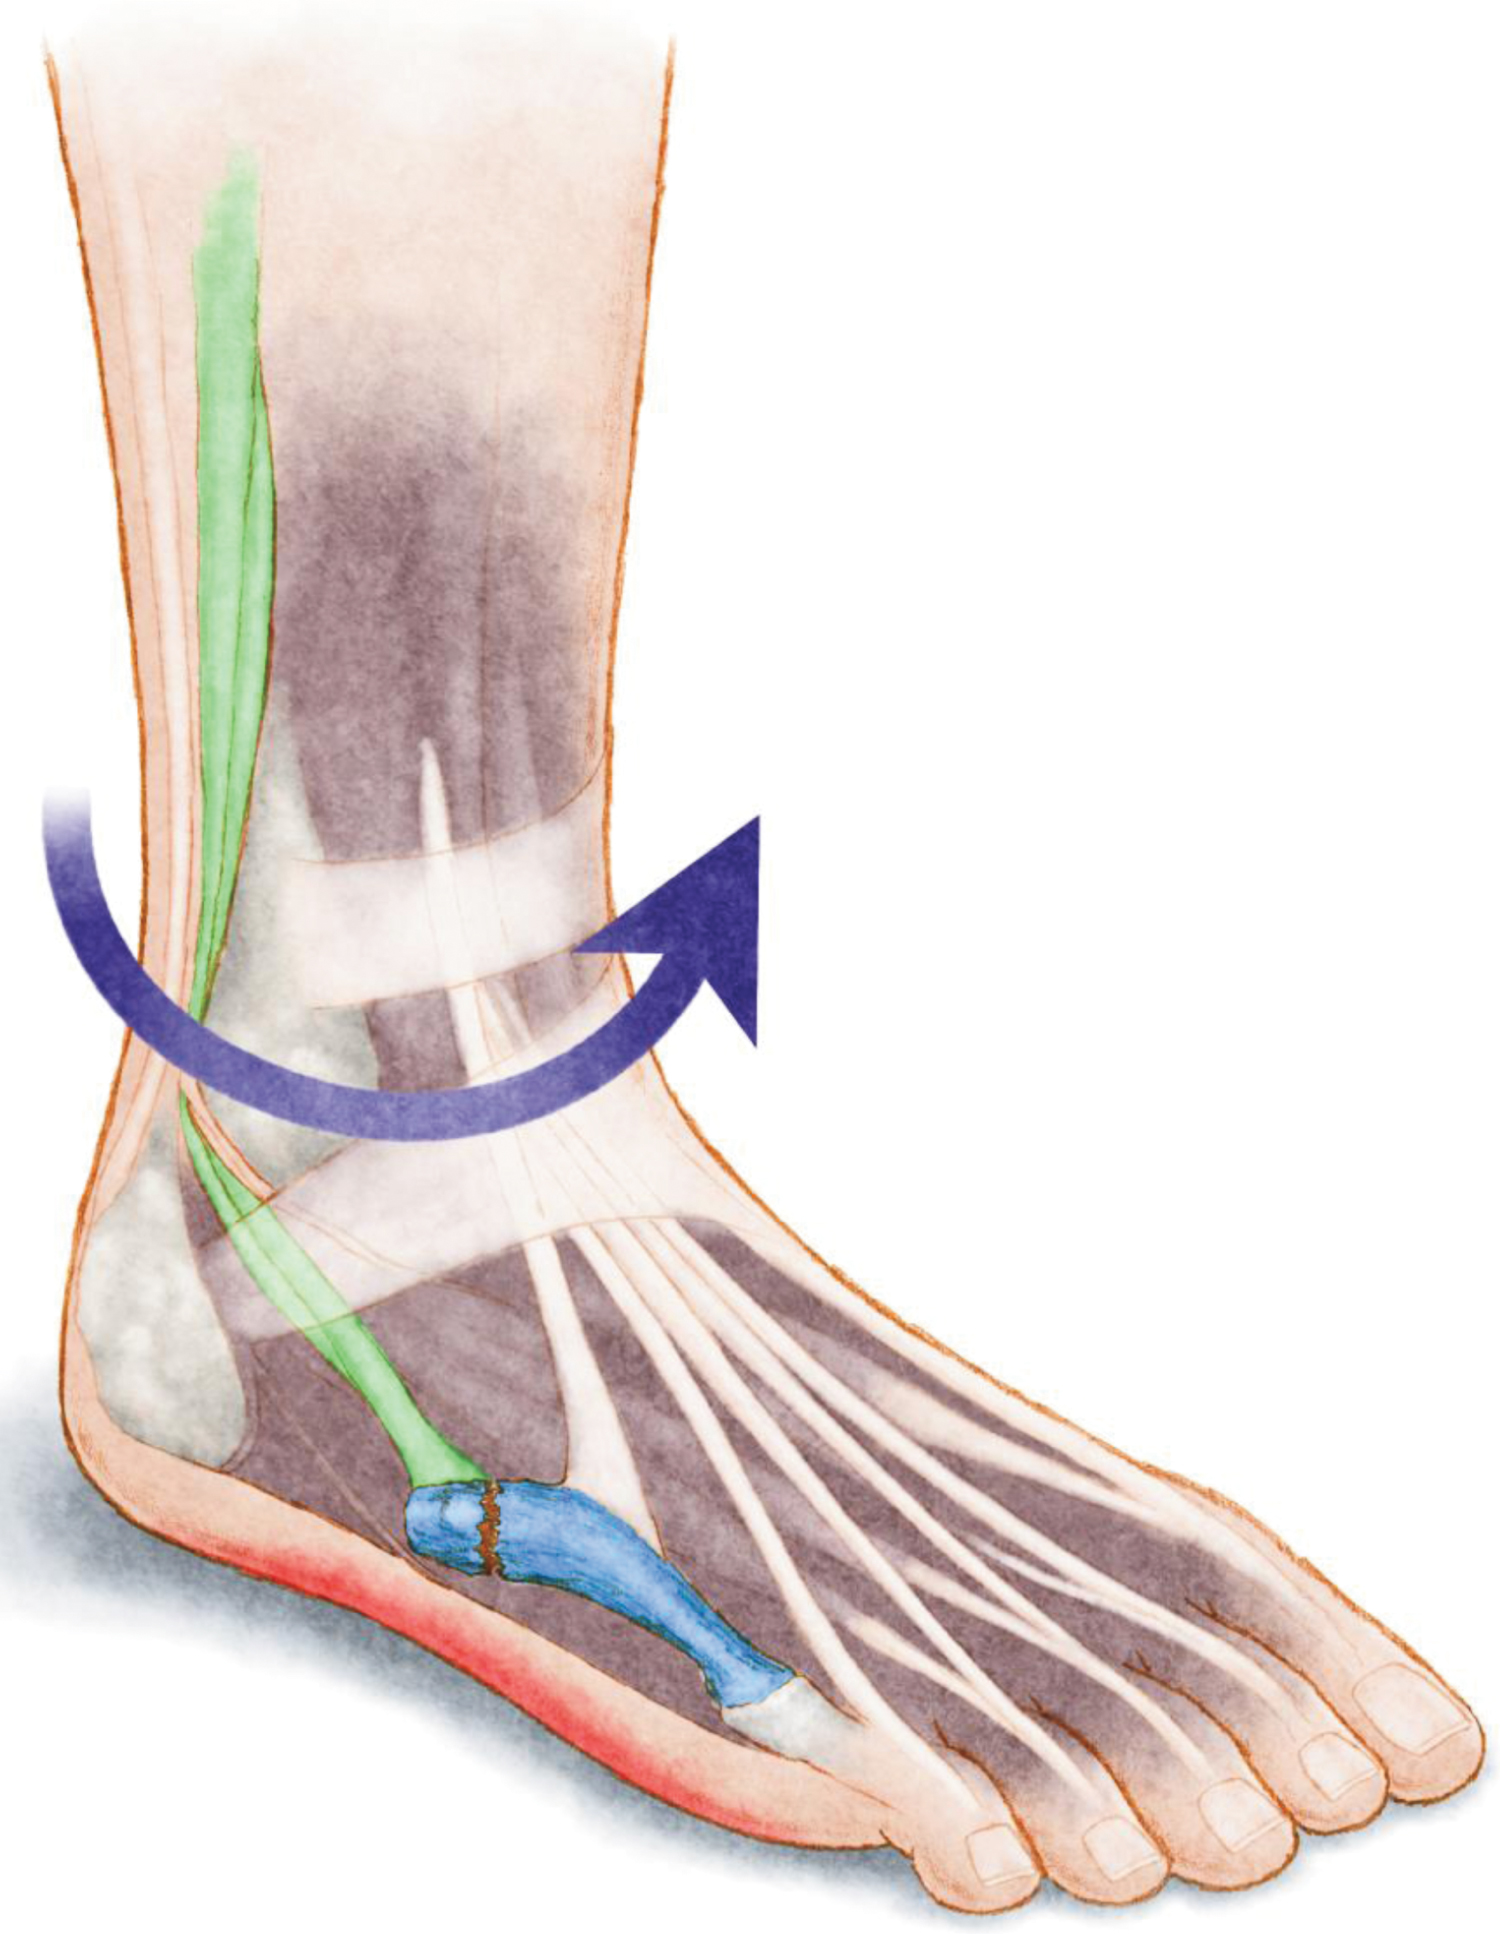

The pathologies associated with subtle cavovarus foot (Figure 7) include ankle instability [3,4,6,8,13,21,30], peroneal tendon pathologies [2,3,8,13,14], stress fractures [6,13] especially at the 5th metatarsal head [3,4], plantar fasciitis [3,8,10], ankle arthritis [11], forefoot equines [3,6], osteochondral talar lesion [8], mechanical metatarsalgia [8,10,11], hallux sesamoid disorders [3,4,8,14], Morton's neuroma [8,14], hallux valgus [8], and pain on the lateral aspect of the foot [6,10,11,13]. The Achilles tendon, which becomes a secondary inverter, is commonly pathologic as well [8,13,14].

Figure 7: Anatomical illustration showing the most frequent injuries observed in subtle cavovarus feet: Ankle instability (purple arrow), peroneal tendinopathy (green), plantar fasciitis (red), and stress fracture of the 5th metatarsal bone (blue). View Figure 7